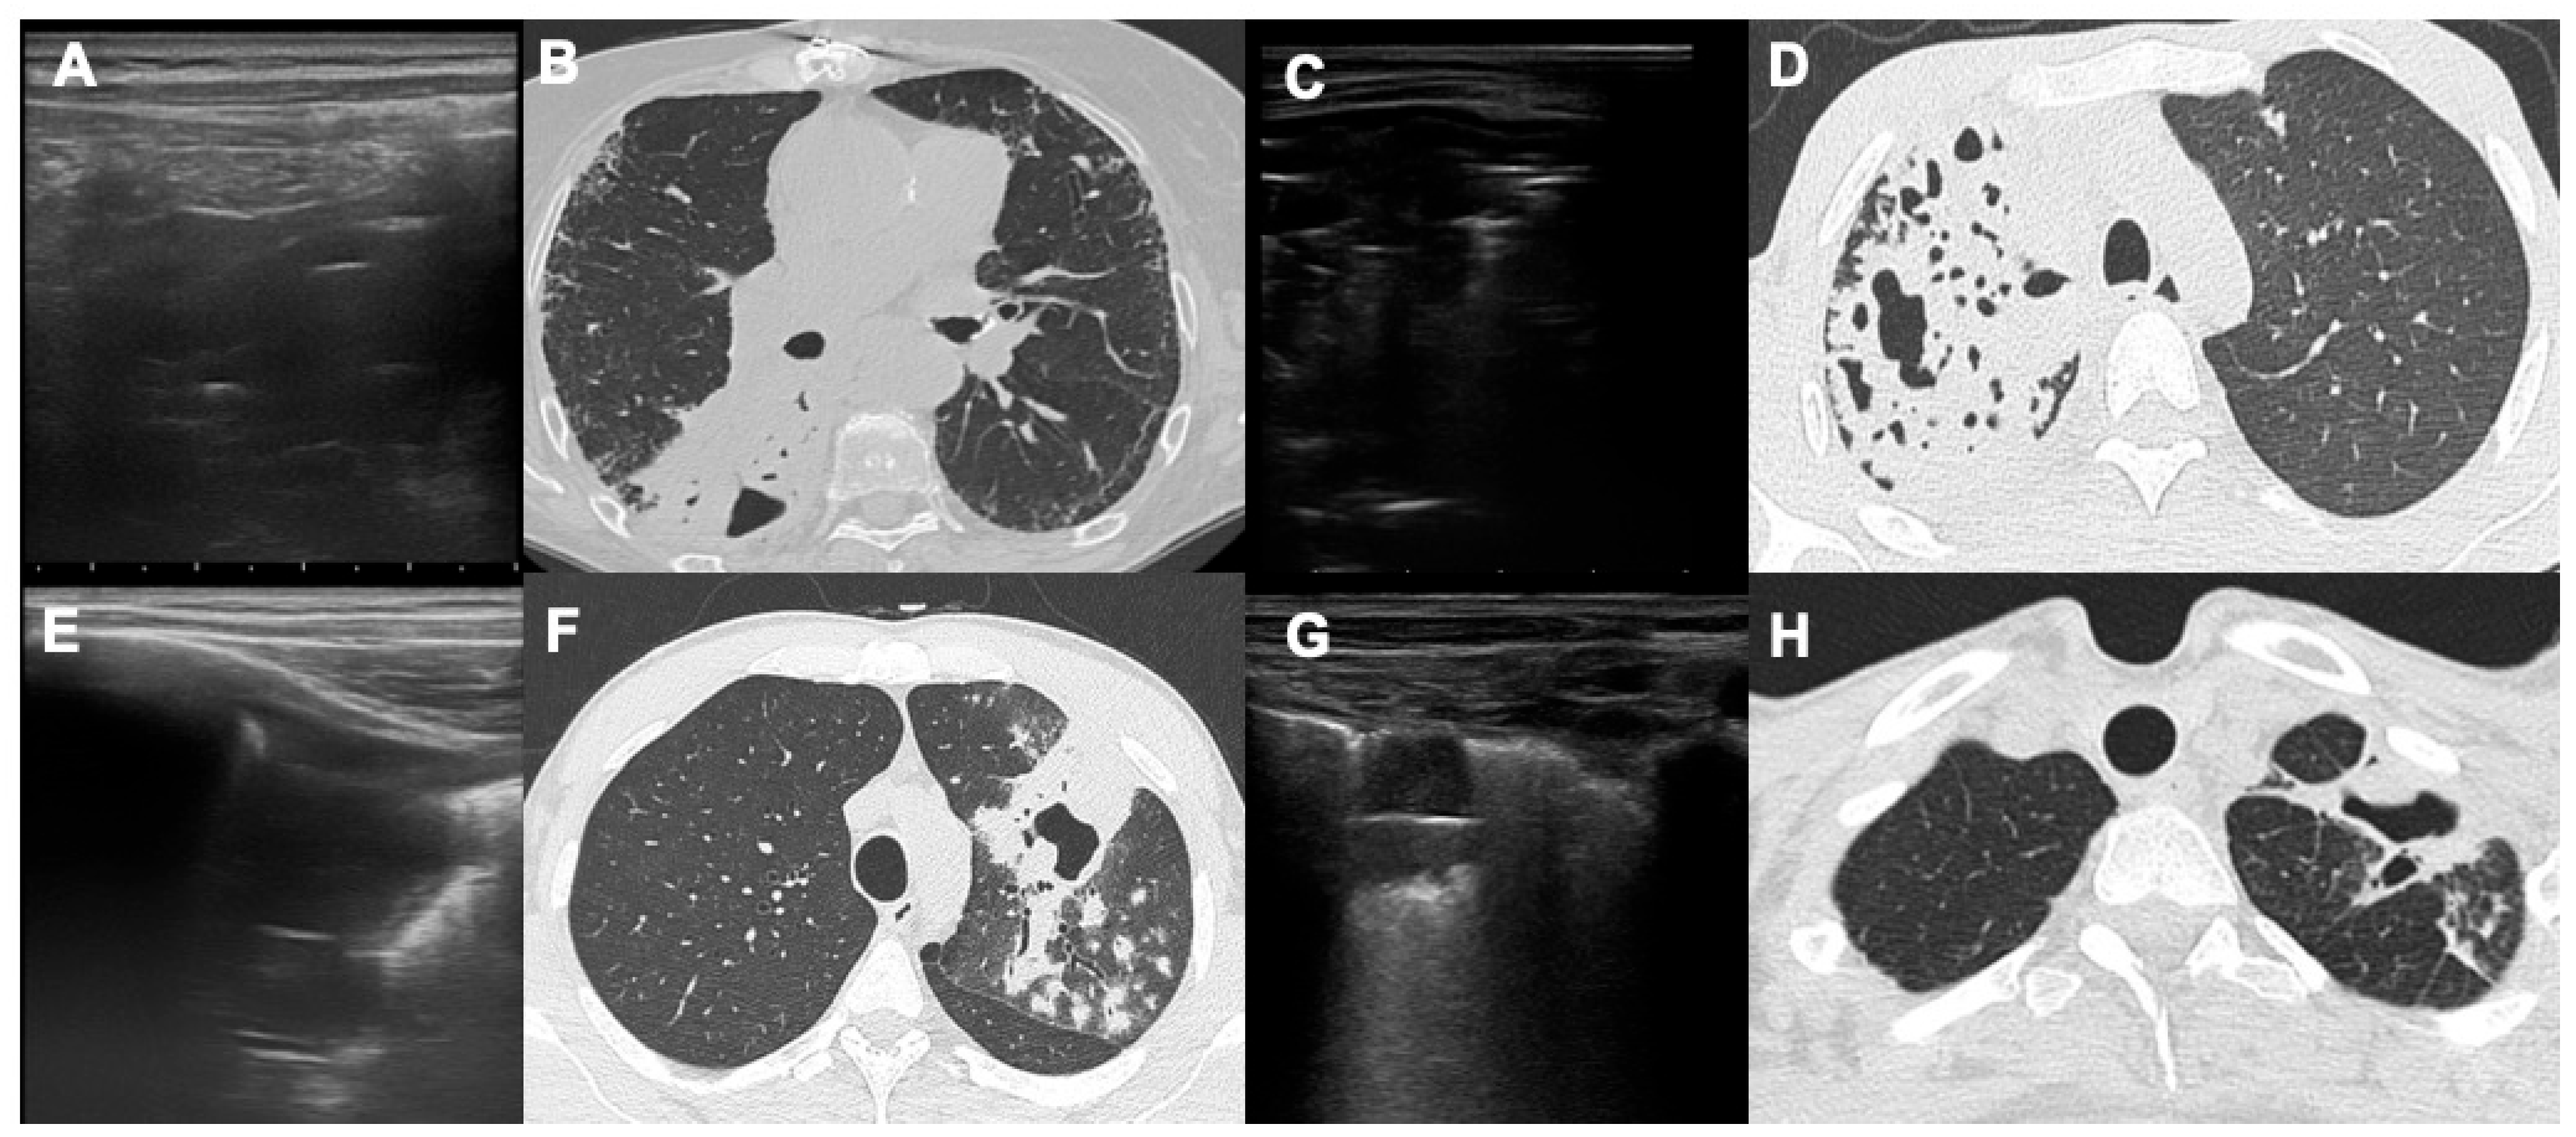

Parenchymal Cavitations in Pulmonary Tuberculosis: Comparison between Lung Ultrasound, Chest X-ray and Computed Tomography

- Giannelli, F.; Cozzi, D.; Cavigli, E.; Campolmi, I.; Rinaldi, F.; Giachè, S.; Rogasi, P.G.; Miele, V.; Bartolucci, M. Lung ultrasound (LUS) in pulmonary tuberculosis: Correlation with chest CT and X-ray findings. J. Ultrasound 2022, 25, 625–634. [Google Scholar] [CrossRef]